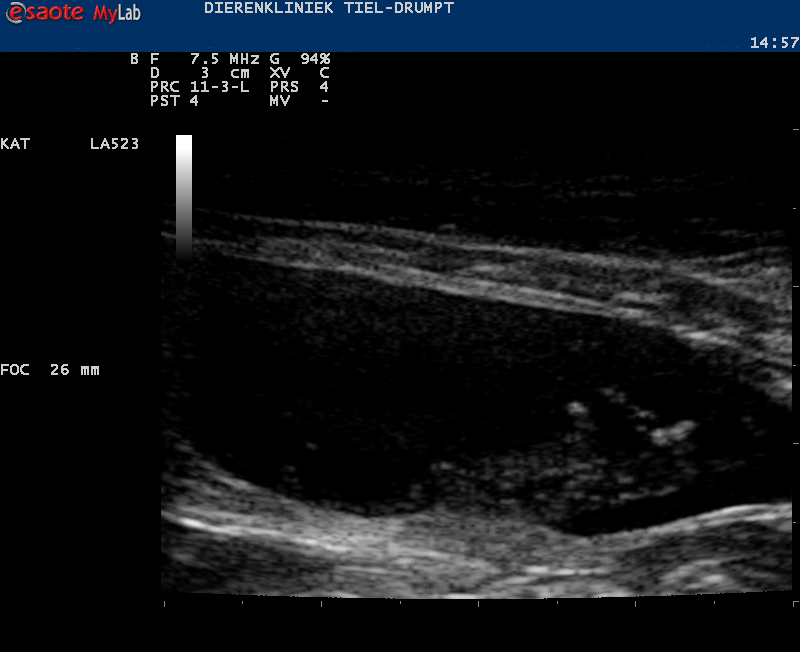

Zo kan er sprake zijn van zwelling of een gezwel bij de penis of een verstopping in de plasbuis door bijvoorbeeld samengeklonterd gruis, een blaassteentje of een plug (dit wordt gevormd door eiwitten, cellen, etc) die een verstopping kunnen geven.Ook structuren in de blaas kunnen de uitmonding verstoppen, zoals steentjes, poliepen, gezwellen, etc.

Let op: een verstopte penis bij de kat is een medisch spoedgeval! Wanneer een kater echt niet meer kan plassen, zal de blaas steeds groter worden. Hierdoor worden de gifstoffen die door de nieren worden uitgescheiden niet meer uitgeplast, waarna deze in het bloed gaan ophopen. Het gevolg is een sloom en ziek dier. Daarnaast rekt de blaas uit, wat schade oplevert voor de blaaswand en de zenuwvoorziening van de blaas.

De kater wordt in slaap gebracht, waarna er geprobeerd wordt om de plasbuis in de penis vrij te krijgen. In de meeste gevallen gaat het om een ontstekingsplug of gruis en in deze gevallen zal er een urinekatheter ingebracht worden. Deze wordt vastgehecht en moet een aantal dagen blijven zitten. De katheter zorgt voor een continue mogelijkheid tot het afvoeren van de urine, waarbij tevens de blaaswand rust krijgt. Na een aantal dagen spoelen en behandelen met medicatie halen we de urinekatheter eruit en zal er gecontroleerd moeten worden of de klachten niet terugkomen.